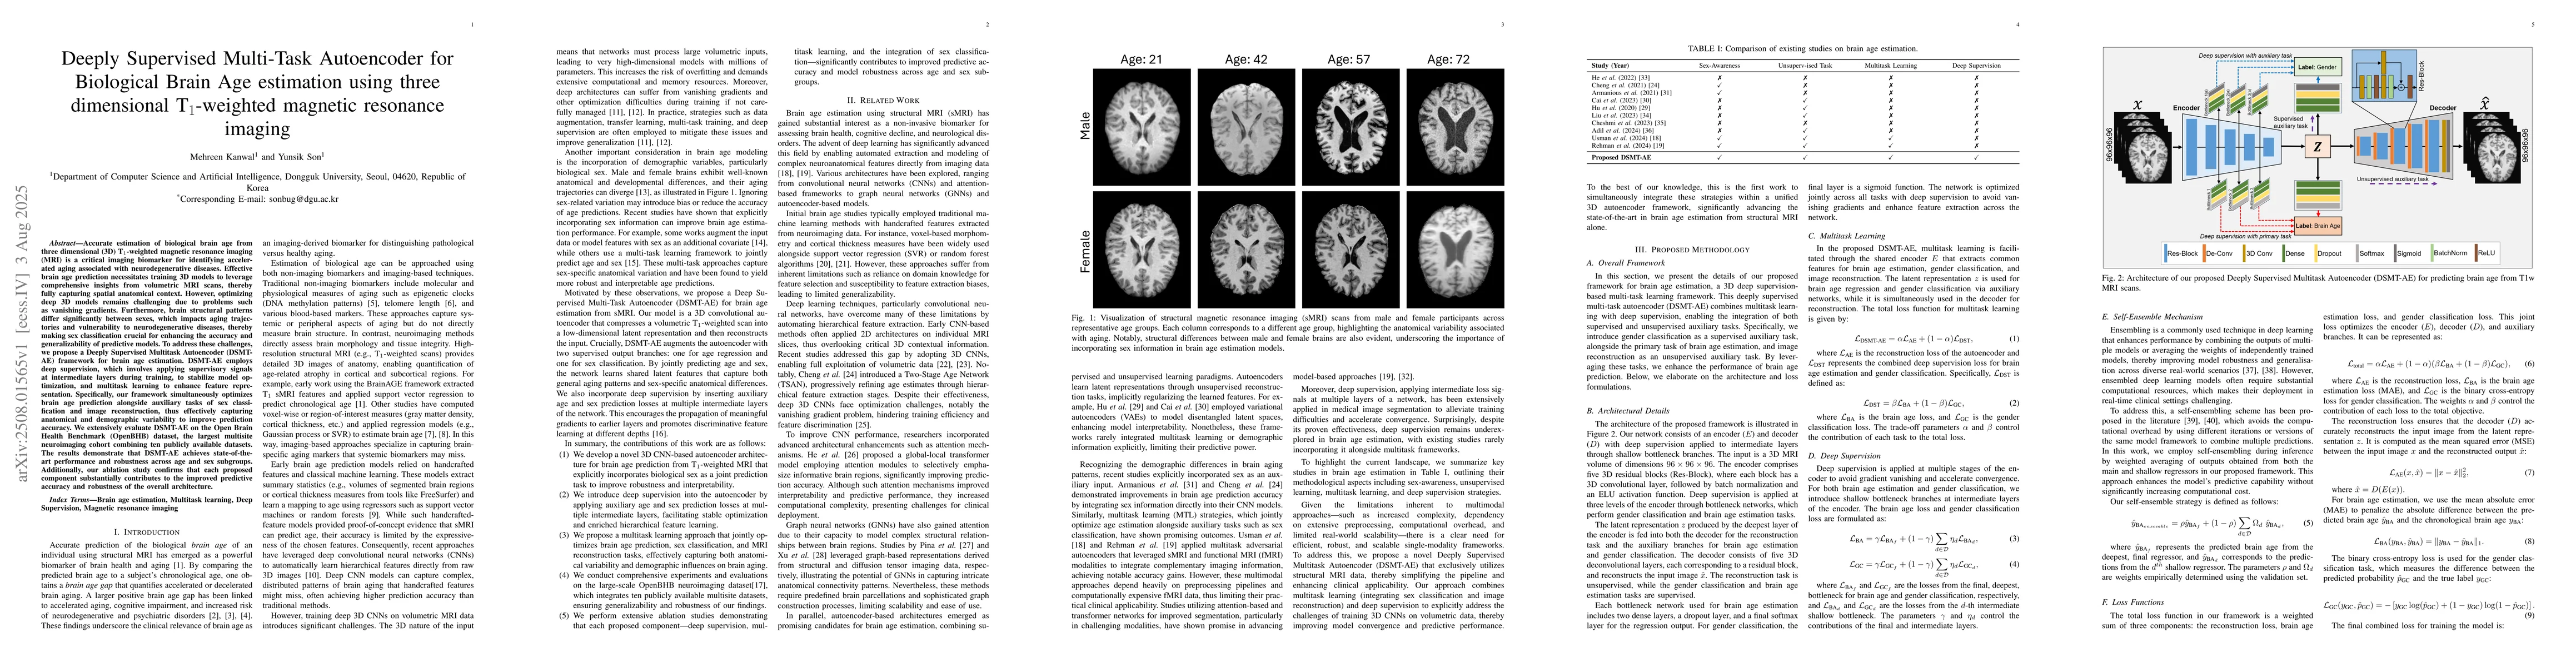

Accurate estimation of biological brain age from three dimensional (3D) T$_1$-weighted magnetic resonance imaging (MRI) is a critical imaging biomarker for identifying accelerated aging associated with neurodegenerative diseases. Effective brain age prediction necessitates training 3D models to leverage comprehensive insights from volumetric MRI scans, thereby fully capturing spatial anatomical context. However, optimizing deep 3D models remains challenging due to problems such as vanishing gradients. Furthermore, brain structural patterns differ significantly between sexes, which impacts aging trajectories and vulnerability to neurodegenerative diseases, thereby making sex classification crucial for enhancing the accuracy and generalizability of predictive models. To address these challenges, we propose a Deeply Supervised Multitask Autoencoder (DSMT-AE) framework for brain age estimation. DSMT-AE employs deep supervision, which involves applying supervisory signals at intermediate layers during training, to stabilize model optimization, and multitask learning to enhance feature representation. Specifically, our framework simultaneously optimizes brain age prediction alongside auxiliary tasks of sex classification and image reconstruction, thus effectively capturing anatomical and demographic variability to improve prediction accuracy. We extensively evaluate DSMT-AE on the Open Brain Health Benchmark (OpenBHB) dataset, the largest multisite neuroimaging cohort combining ten publicly available datasets. The results demonstrate that DSMT-AE achieves state-of-the-art performance and robustness across age and sex subgroups. Additionally, our ablation study confirms that each proposed component substantially contributes to the improved predictive accuracy and robustness of the overall architecture.